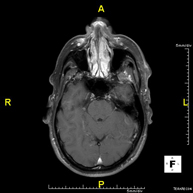

- RM Cerebral (craneal)

Prueba diagnóstica no invasiva que consiste en la obtención de imágenes de alta definición anatómica del cerebro mediante el empleo de un campo electromagnético y ondas de radio (con un emisor y un receptor). No utiliza radiación ionizante. Indicaciones: problemas vasculares, pérdida de memoria, epilepsia, cefalea, malformaciones, sospecha de tumor, meningitis. - RM Cais

- RM Cráneo

Prueba diagnóstica no invasiva que consiste en la obtención de imágenes de alta definición anatómica del cráneo mediante el empleo de un campo electromagnético y ondas de radio (con un emisor y un receptor). No utiliza radiación ionizante. En ocasiones se deberá emplear contraste paramagnético (Gadolinio) para completar el estudio. - RM Cuello